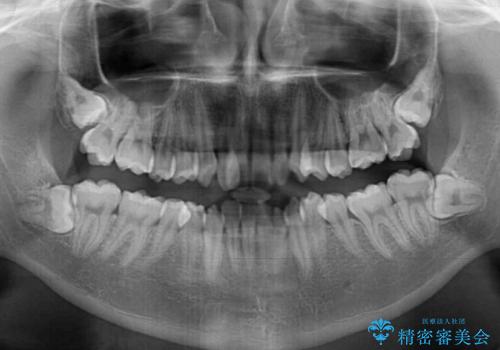

全顎的なクロスバイト 補助装置を用いてワイヤー矯正

前歯のクロスバイトや八重歯の他に、左右最後臼歯のシザーズバイト(鋏状咬合)が認められました。

シザーズバイト改善のために補助装置を使用しながら、ワイヤー装置にて全体の歯列を整えることとしました。